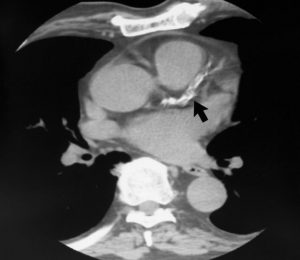

With Heart CT, we can detect and measure the size and density of calcified plaque, presenting that as a quantitative score. The higher the calcium score the greater the amount of underlying CAD and the greater the risk of a subsequent cardiac event.

Normal Arteries